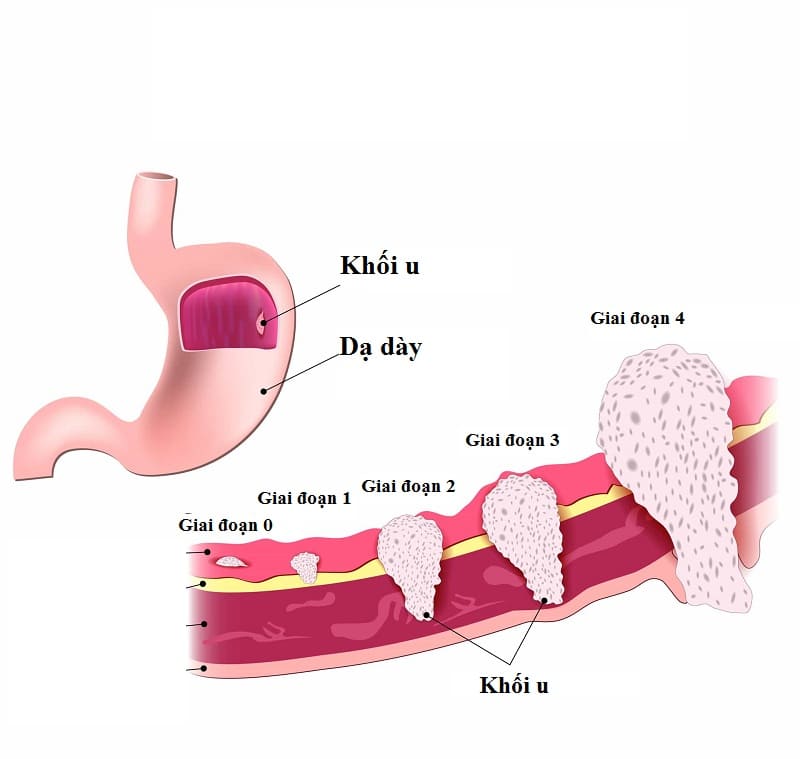

– Trong ung thư dạ dày :

+ Ở giai đoạn đầu: nồng độ Ca 72 – 4 trong máu có tăng vượt trên mức bình thường, tỷ lệ có kết quả tăng ở các bệnh nhân chỉ khoảng 10% – 20% cùng với các triệu chứng lâm sàng ở giai đoạn này chưa rõ ràng triệu chứng lâm sàng nên xét nghiệm thường đóng vai trò quan trọng trong định hướng chẩn đoán bệnh.

+ Ở giai đoạn u tiến triển: nồng độ CA 72 – 4 thường tăng cao và nhanh chóng, có thể tăng trên 100 U/ml. Dấu hiệu ung thư rõ rệt, bệnh tiến triển nhanh.

Ảnh: Các giai đoạn phát triển của ung thư dạ dày